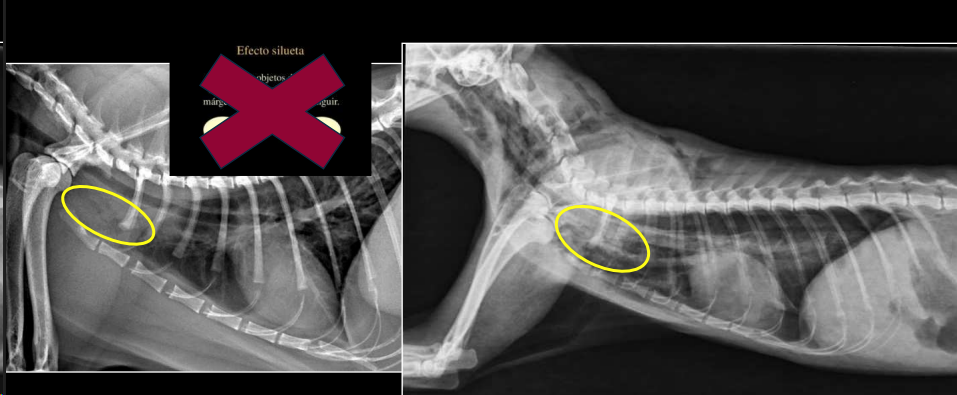

Efecto silhueta: cuando dos objetos de la misma densidad están en contacto, sus margenes no se pueden distinguir. No los distinguimos, los valoramos en grupo, buscamos cambios de tamaño, opacidad o de tamaño

2. Neumomediastino

- Aire en mediastino craneoventral.

- Mayor visualización de estructuras mediastínicas en vez de ver efecto masa en la zona mediastinica craneal, presencia de negros en la zona craneal y mejor visualización de vasos y traquea.

- Enfisemas subcutaneos suelen ocurrir, quedando aire entre las fascias y subcutaneo. Incluso puede pasar a la cavidad abdominal.

- “Tracheal stripe sign”.

- Puede coexistir con enfisema subcutáneo, neumotórax o neumoretroperitoneo.

- Generalmente por rotura traqueal (A veces por rotura esofágica)

- Es la unica forma de diagnosticar un neumodiastino.